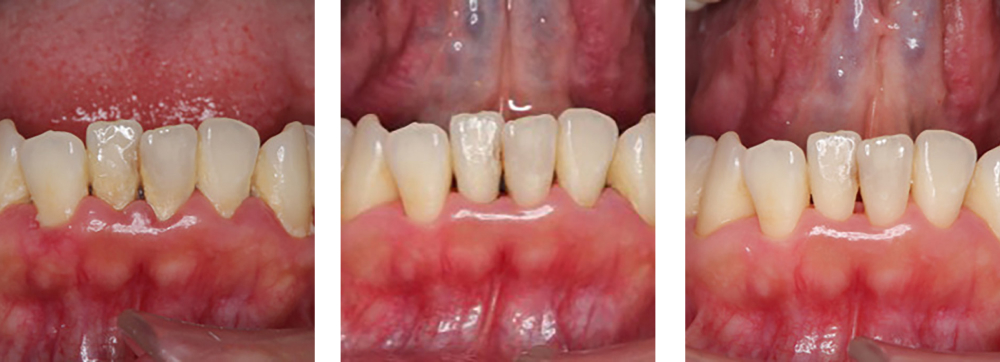

| 治療内容 | 歯磨き指導を行い、歯肉の発赤・腫脹が改善されたため歯石除去を行った |

|---|---|

| 治療期間・回数 | 2カ月・3回 |

| 費用 | 保険適用となります |

| リスク・副作用 |

|